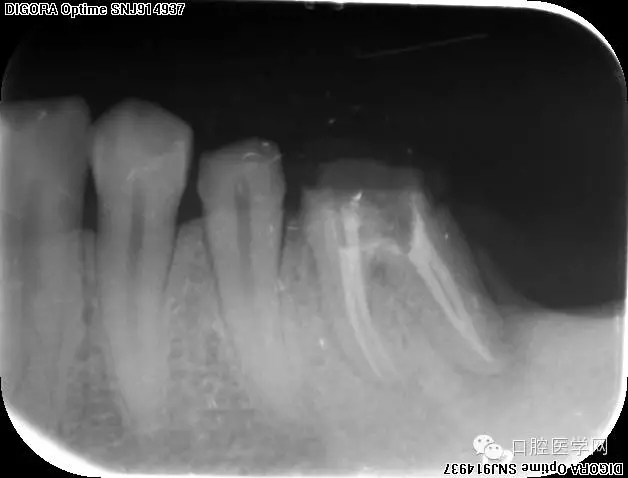

根充,拍片。

根管充填成功標(biāo)準(zhǔn)是X線片示根管充填嚴密,充填材料距根尖孔約1 mm 以內(nèi),允許少量根管糊劑超填。根管無側(cè)穿、無異物和器械分離。

理想療效成功標(biāo)準(zhǔn):治療后無長時間疼痛、腫脹,自覺癥狀消失,竇道愈合,患牙咀嚼功能正常。治療后6個月一24個月,骨吸收區(qū)縮小或消失。